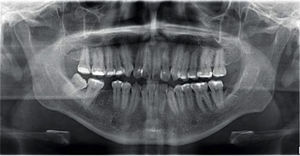

Second order bends were made for root parallelization at the level of the lower right second molar, in which a slight root resorption occurred with no gingival recession.

At the end of orthodontic treatment good occlusal stability, bone status and molar inclination, torsion and rotation were obtained.

Extraoral examination revealed a proper facial balance and profile, a wide smile and the final orthopantomography, an acceptable root parallelism (Figures 6 to 10).